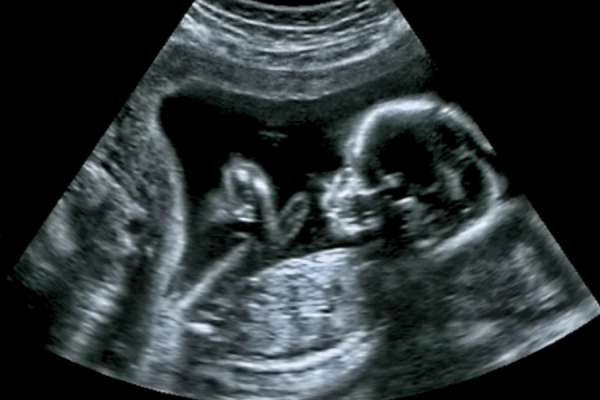

«Un nuevo estudio científico ha encontrado diferencias significativas en las formas en que los cerebros de los fetos masculinos y femeninos funcionan ya antes del nacimiento.

Los investigadores realizaron resonancias magnéticas en fetos humanos en el útero, estudiando la conectividad funcional y las conexiones neurológicas entre diferentes áreas del cerebro, tanto para hombres como para mujeres. Encontraron conexiones entre partes de los cerebros femeninos que eran casi inexistentes en los cerebros masculinos.

«El presente estudio demuestra por primera vez que el desarrollo de la conectividad funcional del cerebro fetal varía con el sexo«, han escrito los investigadores, concluyendo que las redes cerebrales fetales que observaron probablemente constituyen los «bloques de construcción» para el desarrollo cerebral durante el resto de la vida del bebé.